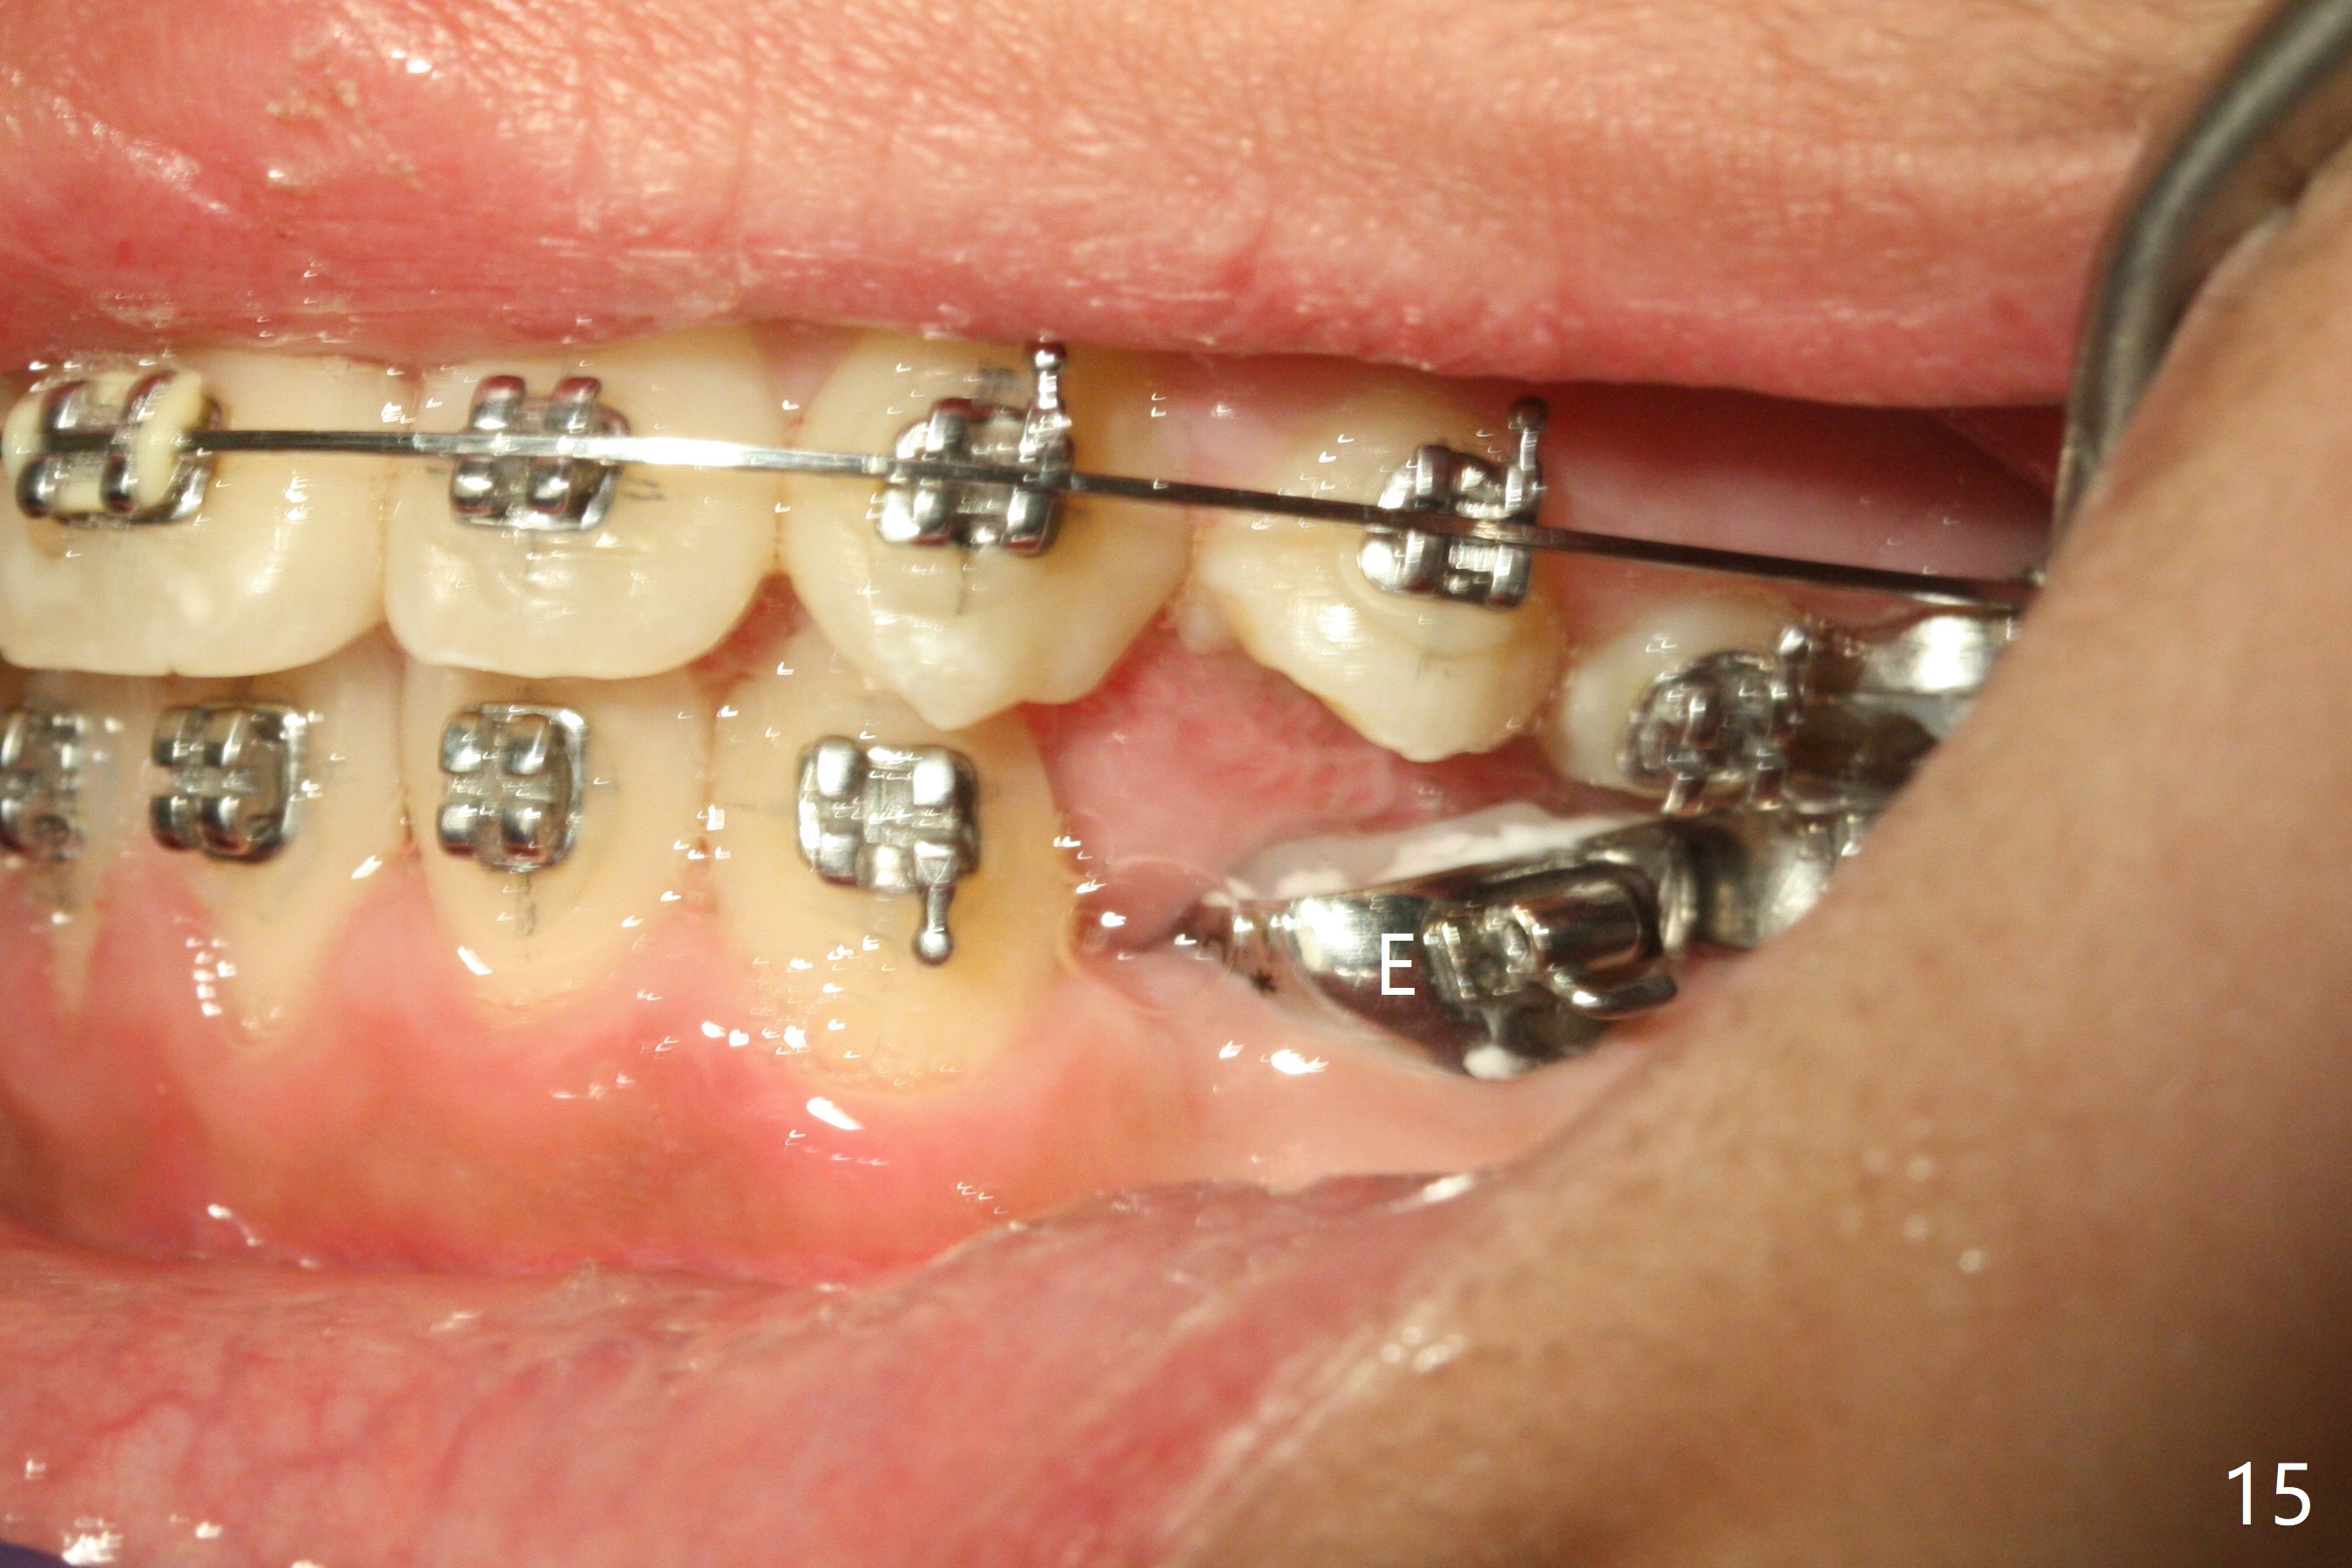

Eight months post banding, the interdigitation on the right side seems to be within normal limit (Fig.10), while the lower dental midline appears to be deviated to the left (Fig.11) with anterior overjet (Fig.12). The left canines remain Class II; open coil spring is placed between LL3-6 with intention to reduce anterior overjet and correct the lower midline deviation (Fig.13). Four weeks later, LL3 does not seem to be mesialized. It appears that the long open coil spring between LL3-6 is not effective. A molar band is added to LL E (Fig. 14,15). When a molar band is placed in LL7, an upper niti wire will be placed in the lower arch to expand the arch. When arch wire turns into thicker one, place open coil spring between LL3 and E.